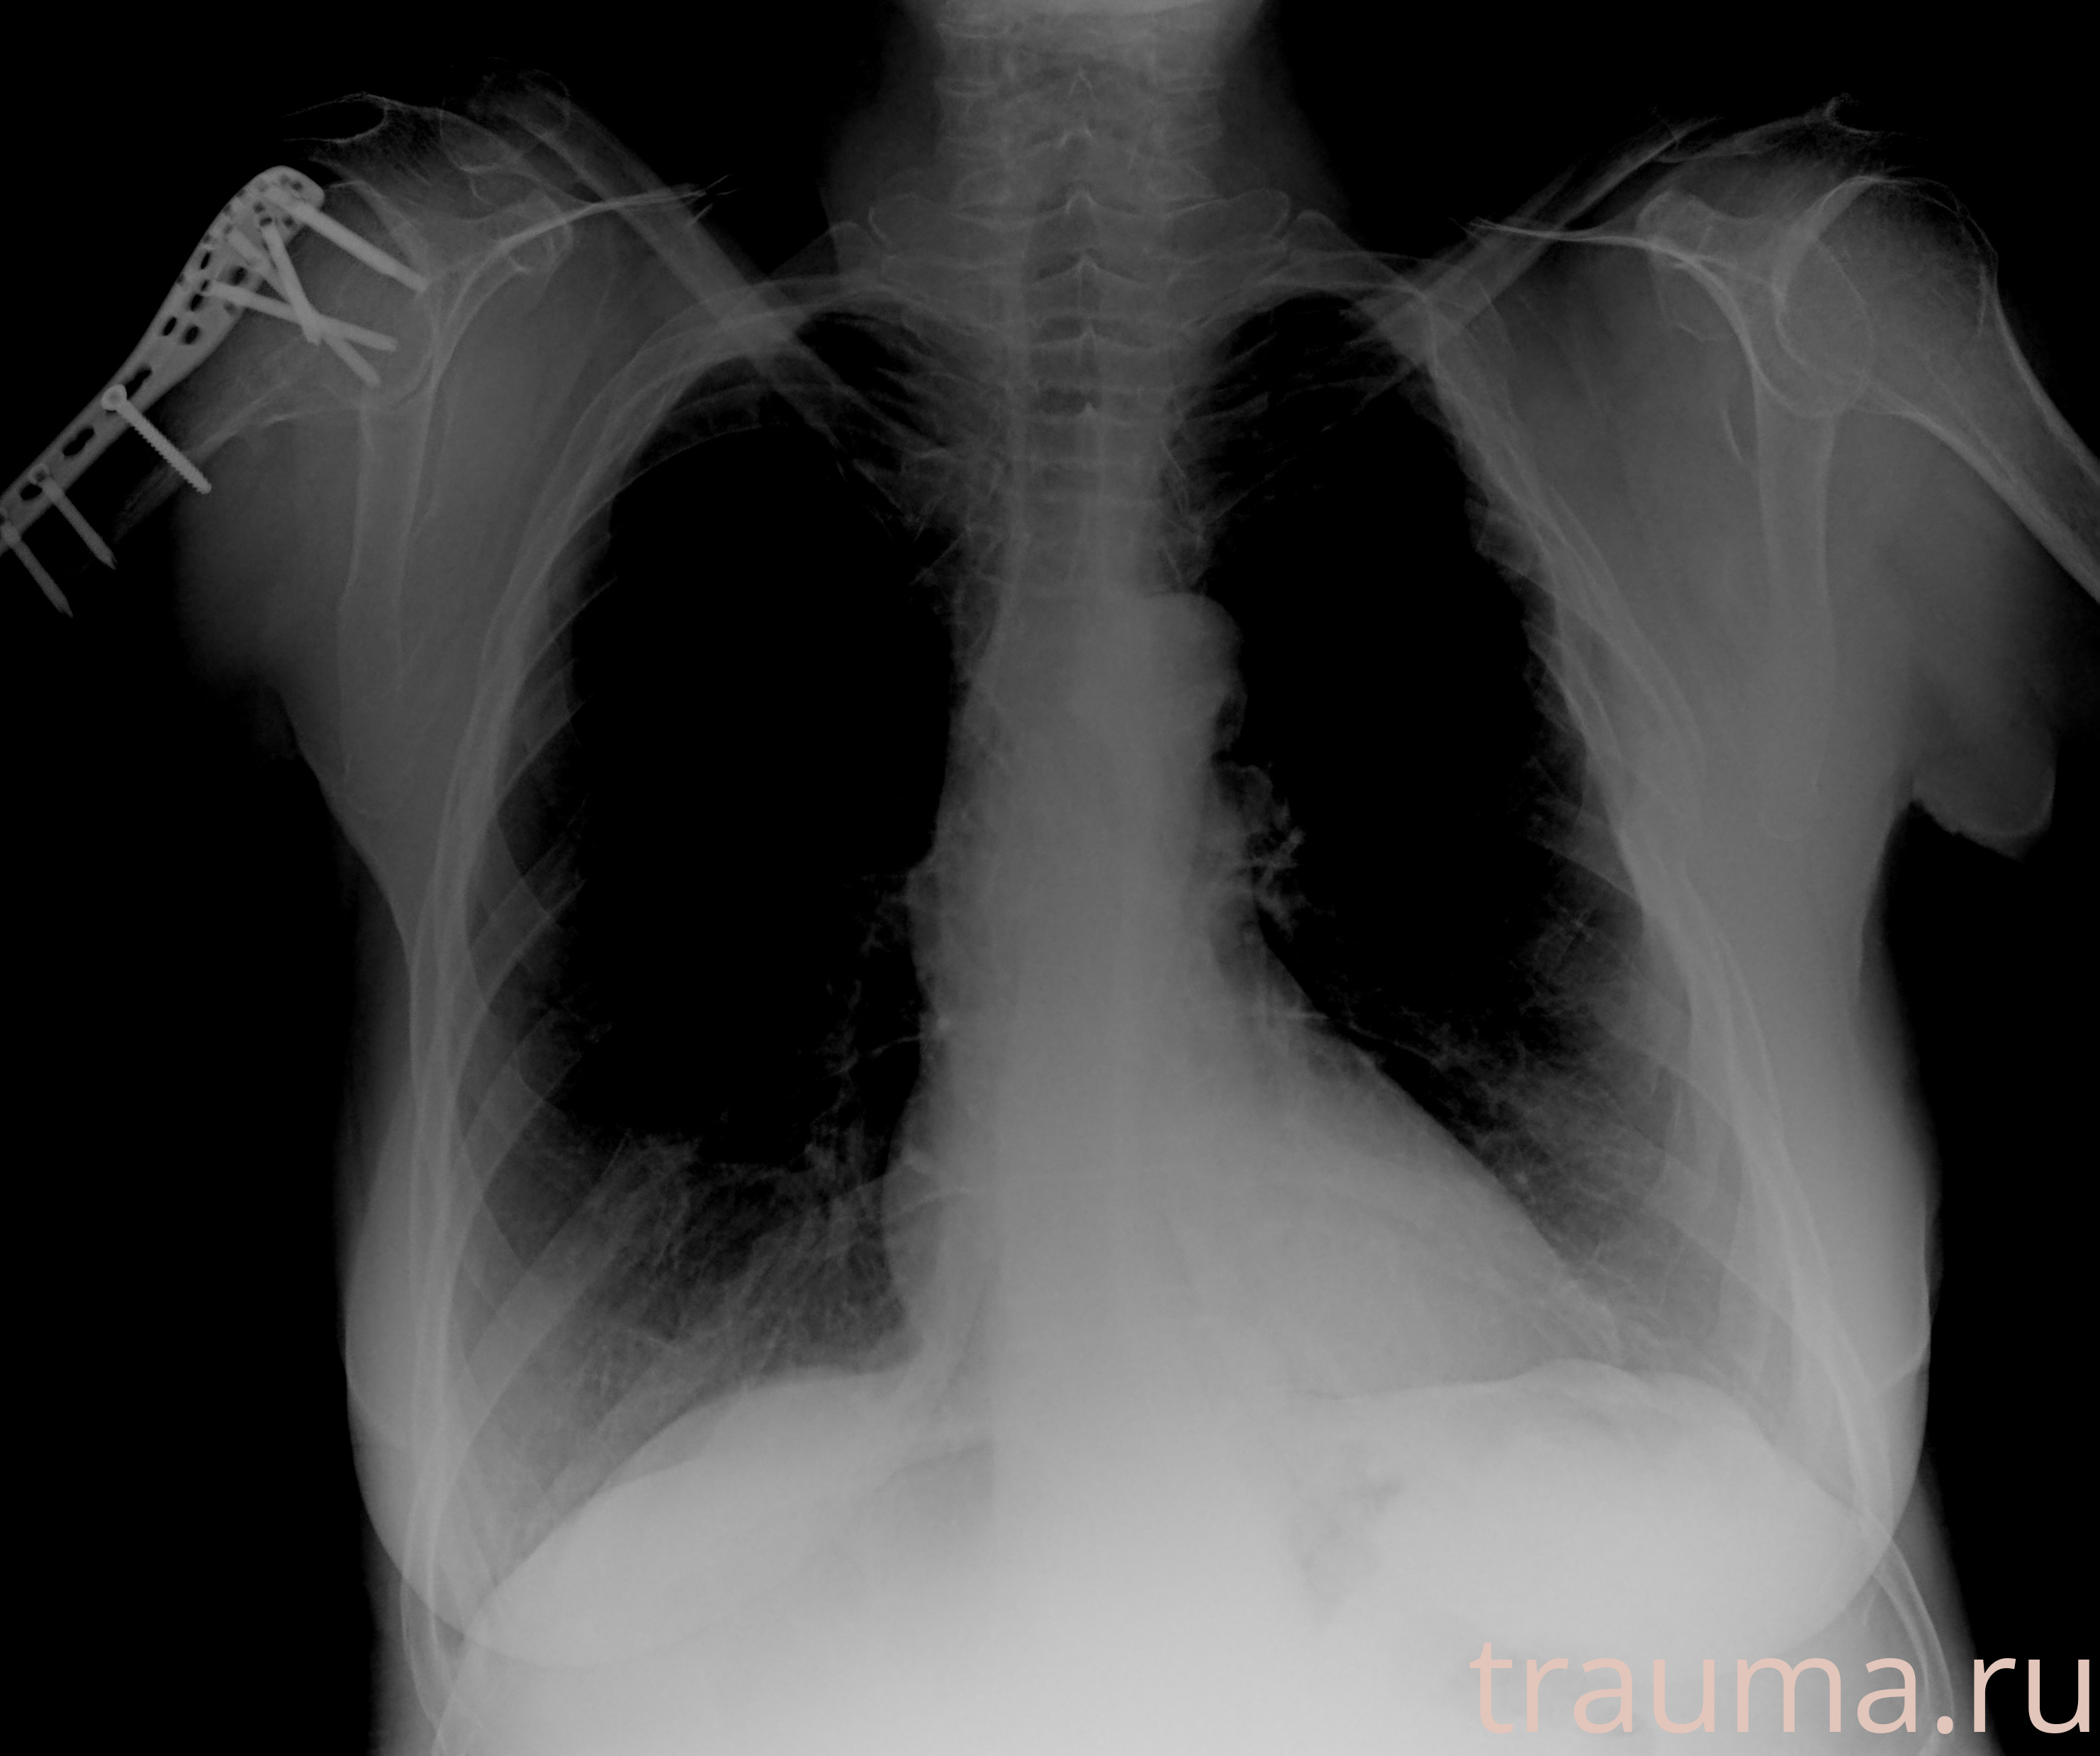

Рентгенограммы

Рентген на дому: по вашему адресу приезжает врач-рентгенолог, травматолог-ортопед с мобильным рентгеновским аппаратом, проводит диагностику травмы или заболевания, делает необходимые рентгенограммы, дает рекомендации по дальнейшему лечению. Получить качественные снимки в домашних условиях возможно благодаря уникальной методике, разработанной МосРентген Центром для института  Склифосовского

Яркость: 1   Контраст: 1   Инвертировать: 0 Увеличение: 1

Перетаскивайте мышь вверх/вниз для контраста, влево/право для яркости. Прокрутка колесом изменяет масштаб. Нажмите Сбросить для возврата к исходному изображению. При увеличении держите мышь в той области, которую хотите рассмотреть.